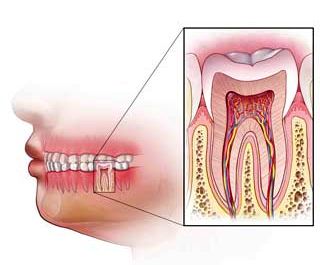

Her dişin ortasından onun beslenmesini ve duyarlılığını sağlayan damar ve sinir paketi geçer. Bu dam ...